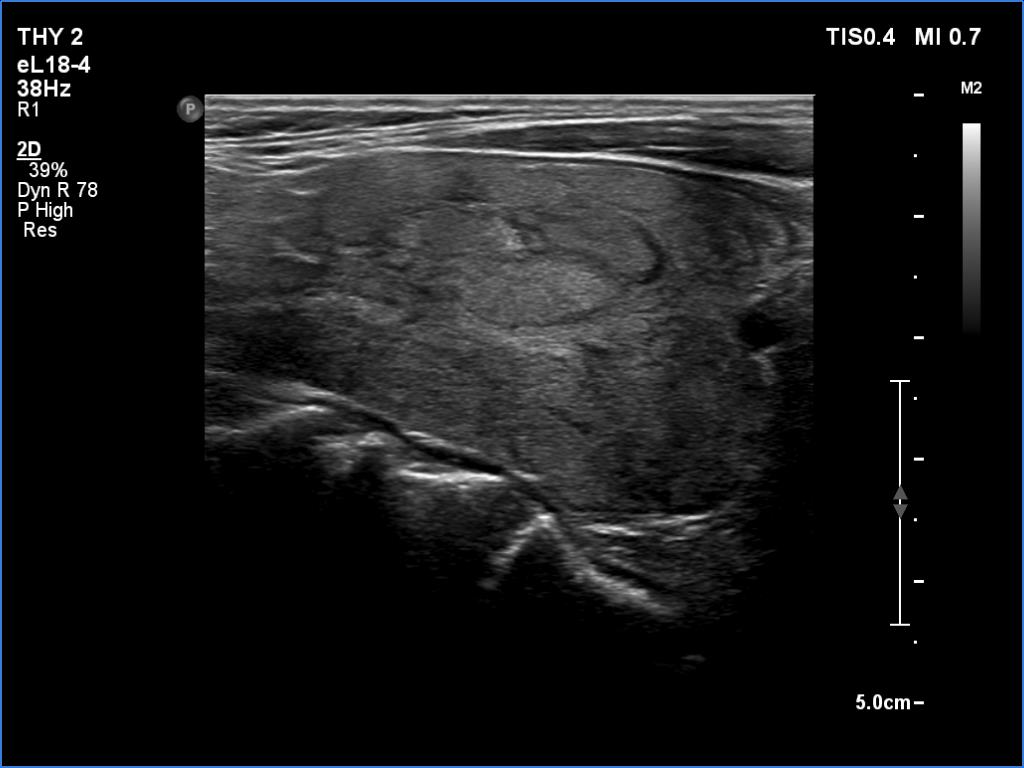

Lymphocytic thyroiditis - case 609

Follow-up investigation 6 years after the first visit (ultrasonographic picture 11)

Left lobe, longitudinal scan.